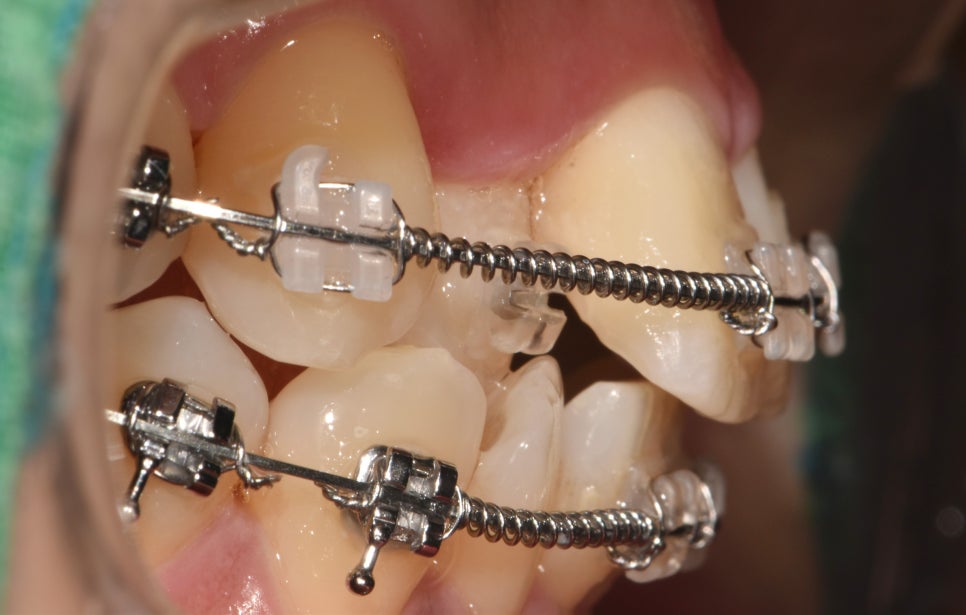

치면에 브라켓을 붙여 어금니를 뒤로 이동시키며

공간을 형성합니다.

틀어져 있던 부분들이 서서히 이동을 시작하며

11번과 13번 사이에 간격을 줌으로써,

12번이 전방으로 나올 수 있는 길을 만들어

반대교합을 서서히 개선해 나갈 수 있습니다.

이에 따라 앞니 뻐드렁니 양상도

점점 후방으로 견인되어 들어가

돌출감을 줄여줄 수 있습니다.